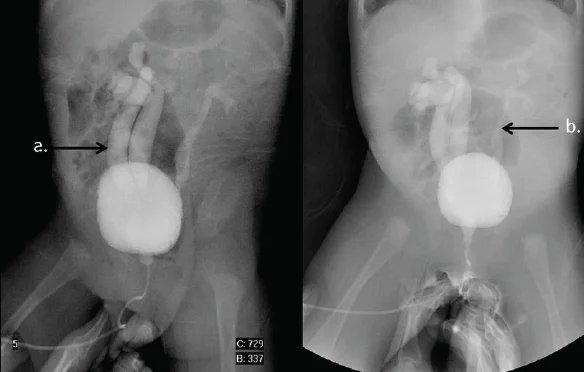

High-resolution digital imaging for detailed cellular analysis.